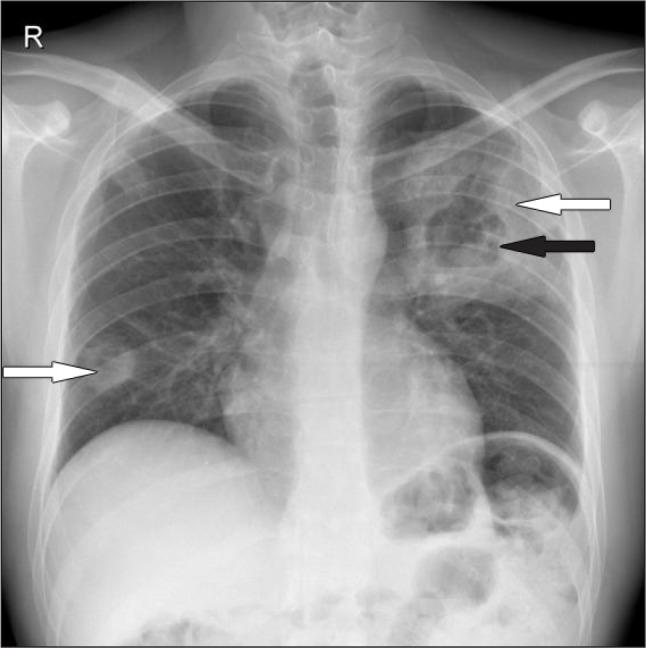

ANCA-associated vasculitis (AAV) is an inflammatory systemic disorder affecting small to medium sized vessels and likely leading to any organ dysfunction. Adequate treatment is important to avoid mortality or severe organ damage. In most cases initial treatment (induction therapy) allows to achieve remission. Induction therapy leads to immunosuppression and may cause severe infections. However, in vasculitis patients even an intensive immunosuppressive therapy is rarely complicated by an invasive fungal infection. We present a case in a 29-year old male patient with newly diagnosed AAV. He suffered a fatal pulmonary complication of the induction immunosuppressive treatment. Pathological (infectious) changes in the lungs were misinterpreted as progression of the vasculitis and he died due to disseminated angioinvasive aspergillosis. A clinical course, imaging and histopathology of this case are described and discussed.

抗中性粒细胞胞浆抗体相关性血管炎(AAV)是一种影响中小血管的炎症性全身性疾病,可能导致任何器官功能障碍。充分的治疗对于避免死亡或严重器官损害很重要。在大多数情况下,初始治疗(诱导治疗)可实现缓解。诱导治疗会导致免疫抑制,并可能引起严重感染。然而,在血管炎患者中,即使是强化免疫抑制治疗也很少并发侵袭性真菌感染。我们报告一例29岁新诊断为AAV的男性患者。他在诱导免疫抑制治疗中出现了致命的肺部并发症。肺部的病理(感染性)变化被误诊为血管炎的进展,他因播散性血管侵袭性曲霉病死亡。本文描述并讨论了该病例的临床病程、影像学和组织病理学情况。